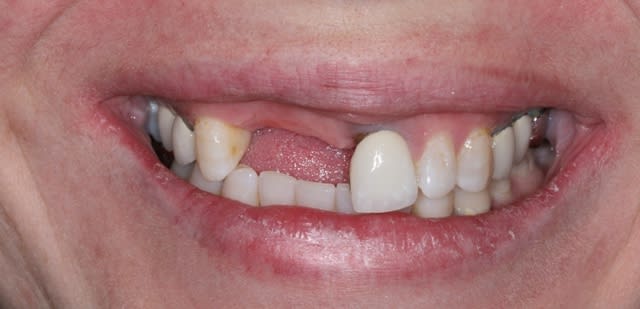

Bon ben j'ai implanté avant d'avoir refait la 21. Du coup j'ai mésialé la pose de 11 pour compenser la distalisation de 21.

Au final je n'ai pas fait de greffe osseuse... et j'ai réalisé une technique de rouleau sur 11-12 mais je reste un peu court à mon goût.

J'ai mis en place des transitoires sur 11-12-21 pour temporiser 3 mois pour voir la maturation des tissus mous.

Je mets quelques photos de la patiente au cab et du prothèsiste d'Epinal.

Les provisoires sont solidaires ? ( bravo pour le parallélisme)

Le zénith de la 21 doit être un peu plus distal pour que le résultat soit plus sympa

(comme tu l'as si bien fit sur la 11, allez quoi, un petit coup de bistouri et hop tu gagnes en esthétique)

Ton protho pourrait maquiller un peu plus les provisoires et éviter les bulles......

Malgré ces petites remarques c'est quand même sympatoche comme tout

On avance dans le cas, j'ai revu la patiente hier.

Elle est satisfaite et moi pas vraiment, comme quoi...

Elle ne veut pas faire de chir mucco gingivale et accepte éventuellement que je fasse une petite chir d'élongation coronaire sur 21 car elle trouve cela surperflux.

Tristesse et difficulté des sourires gingivaux !

J'avais bien raison de me méfier au départ...